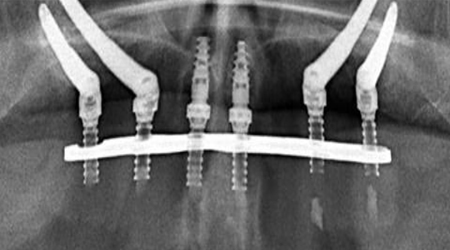

ALL- ON -4 FOR LESS BONE

Upper Jaw/Lower Jaw (Per Jaw)

Technique INR US

4 NOBEL BIOCARE Implants including 2 ANGULATED Implants + IMMEDIATE Provisional Denture + Final Fixed Titanium Hybrid Denture of 12-14 Teeth 350000 5400

4 NOBEL BIOCARE Implants including 2 ANGULATED Implants + IMMEDIATE Provisional Denture + Final Fixed PROCERA Implant Bridge Denture of 12-14 ZIRCONIA Ceramic Crown 500000 7600

ALL- ON -4 WITH ZYGOMA IMPLANTS (FOR MINIMAL BONE)

Upper Jaw

4 NOBEL BIOCARE Implants including 2 ZYGOMA Implants + IMMEDIATE Provisional Denture + Final Fixed TITANIUM HYBRID Denture of 12-14 Teeth 650000 10000

4 NOBEL BIOCARE Implants (QUAD ZYGOMA)+ IMMEDIATE Provisional Denture + Final Fixed TITANIUM HYBRID Denture of 12-14 Teeth 800000 12300

SINUS LIFT PROCEDURE

Indirect 22000 350

Direct SINUS LIFT Procedure 50000 775